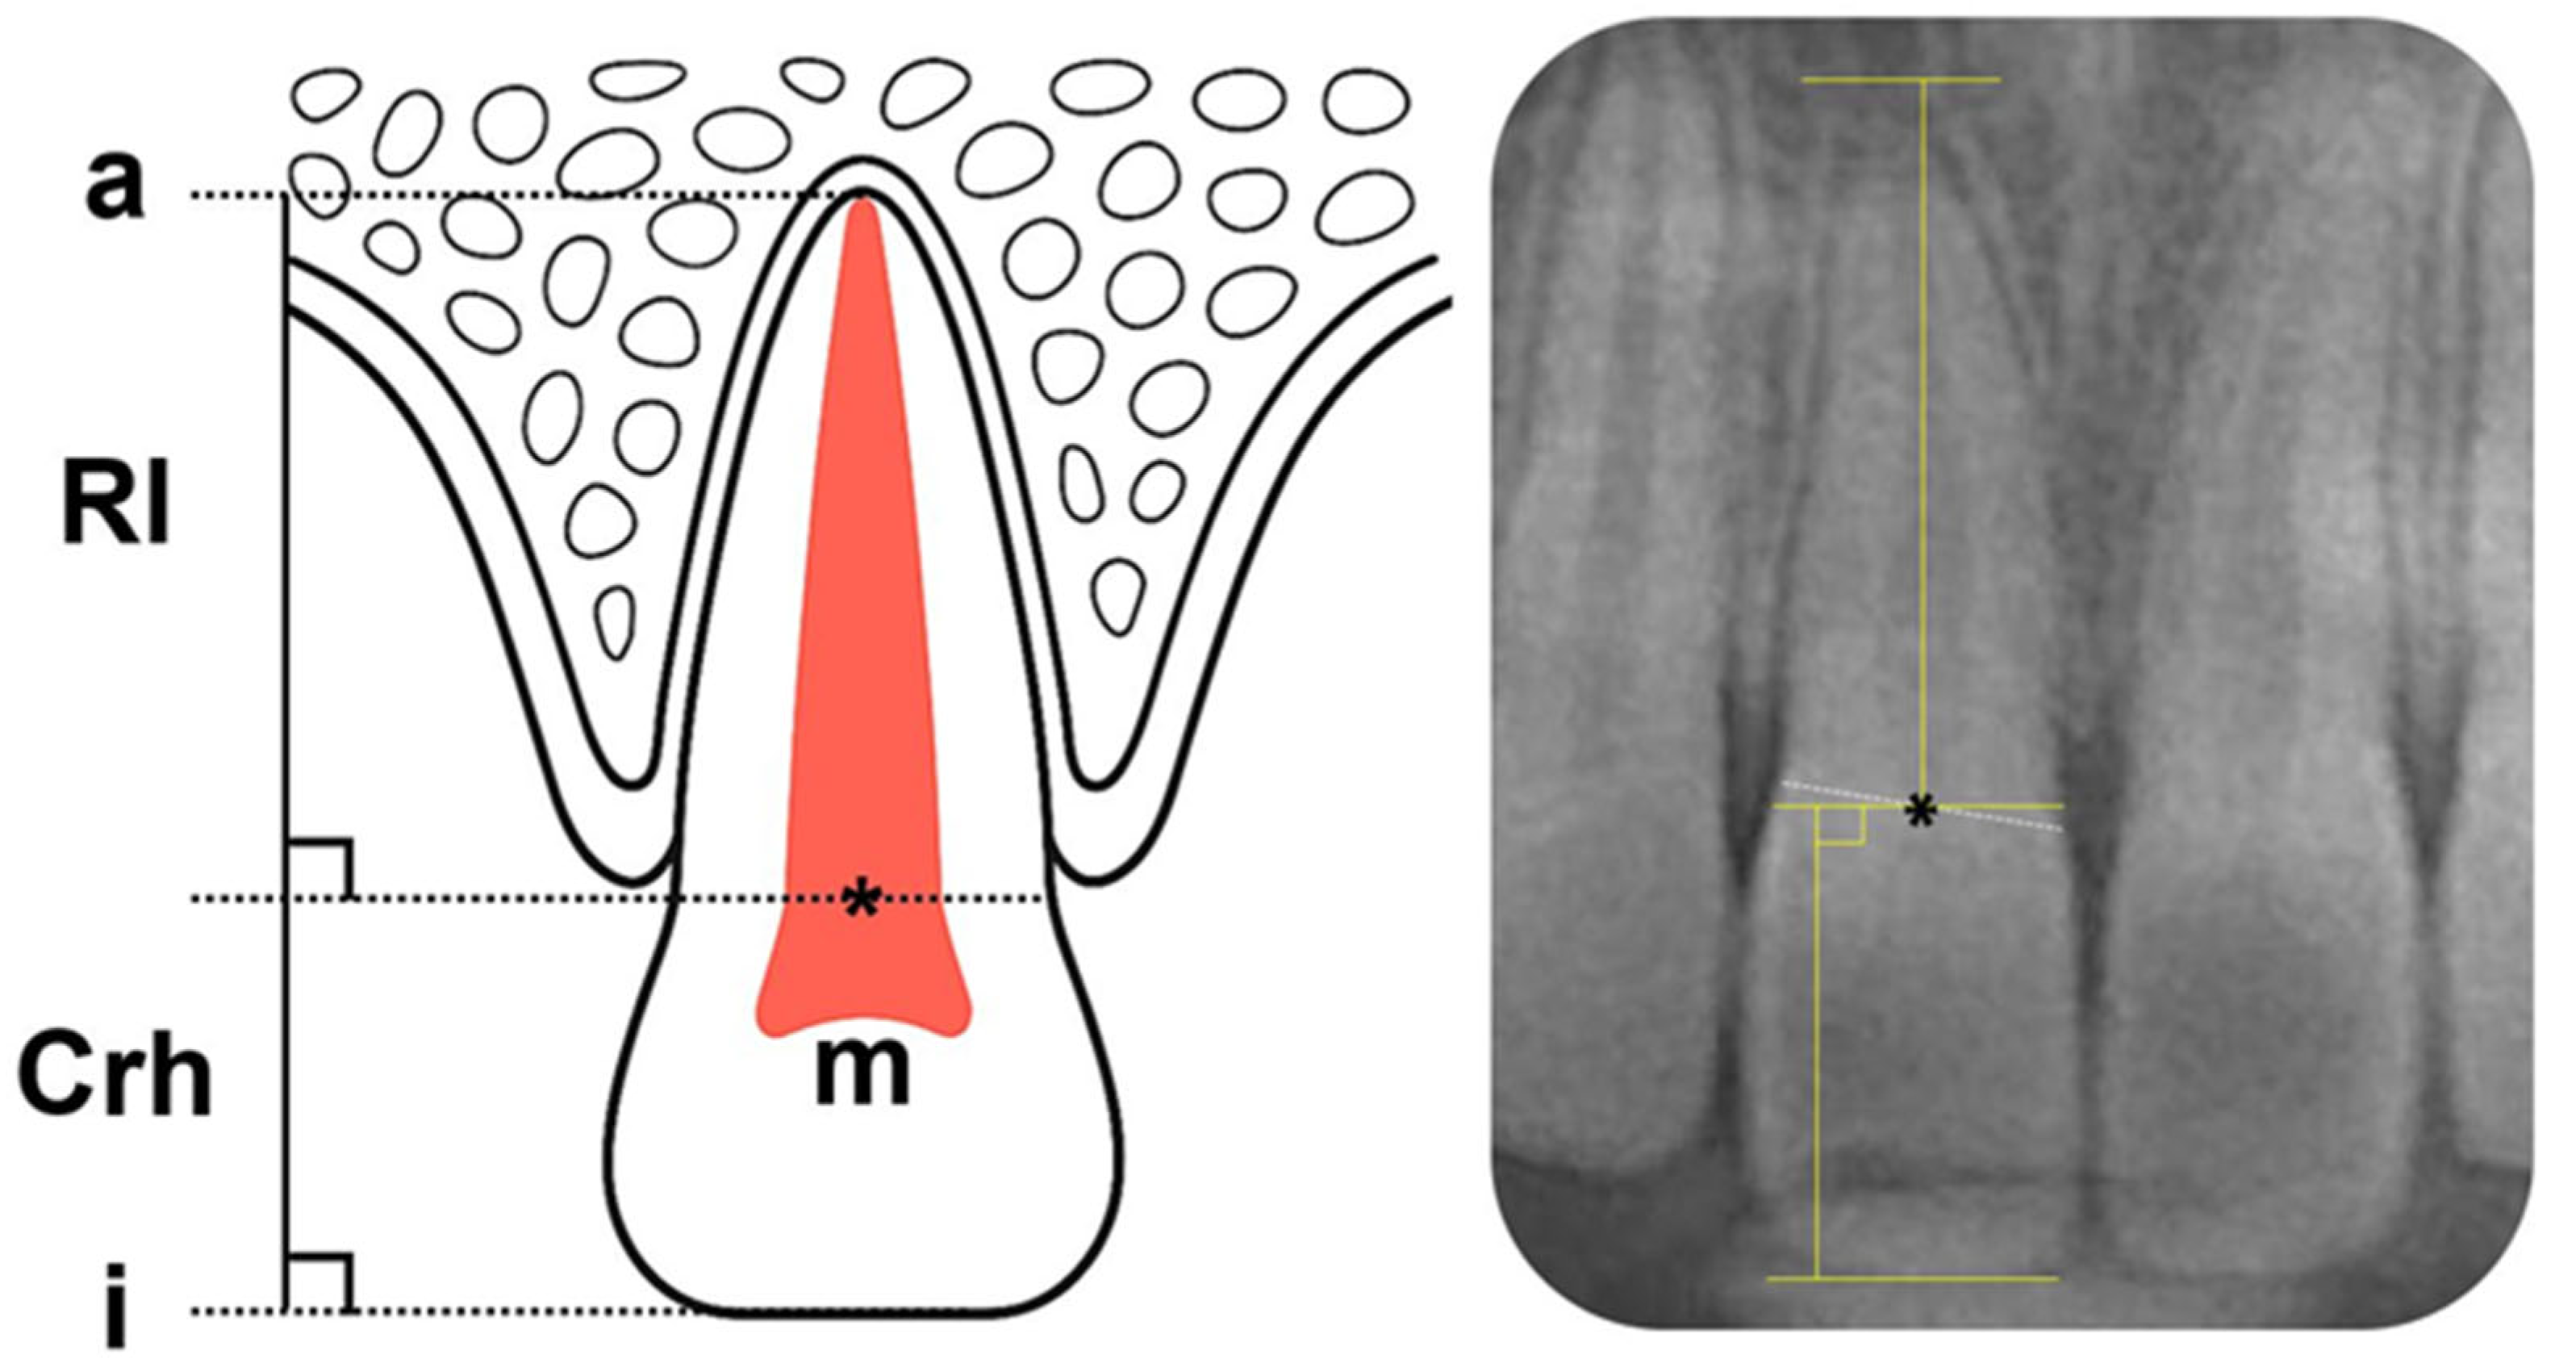

- Linge, B.O.; Linge, L. Apical root resorption in upper anterior teeth. Eur. J. Orthod. 1983, 5, 173–183. [Google Scholar] [CrossRef]

- Sameshima, G.T.; Asgarifar, K.O. Assessment of root resorption and root shape: Periapical vs panoramic films. Angle Orthod. 2001, 71, 185–189. Available online: https://meridian.allenpress.com/angle-orthodontist/article/71/3/185/56474 (accessed on 18 October 2025).

- Yun, H.J.; Jeong, J.S.; Pang, N.S.; Kwon, I.K.; Jung, B.Y. Radiographic assessment of clinical root-crown ratios of permanent teeth in a healthy Korean population. J. Adv. Prosthodont. 2014, 6, 171–176. [Google Scholar] [CrossRef]

- Hölttä, P.; Nyström, M.; Evälahti, M.; Alaluusua, S. Root–crown ratios of permanent teeth in a healthy Finnish population assessed from panoramic radiographs. Eur. J. Orthod. 2004, 26, 491–497. [Google Scholar] [CrossRef] [PubMed]